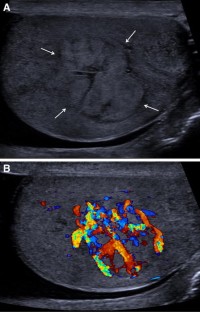

We report a case of a lobular capillary hemangioma in a 66-year-old man, who presented with left testicular pain, with an asymptomatic incidental right testicular lesion found on ultrasonography. The sonographic examination demonstrated a heterogeneous mainly iso-echoic intratesticular lesion with marked vascularity on the color Doppler examination. Further evaluation with contrast-enhanced ultrasound and strain elastography was performed; the multiparametric imaging suggested a benign tumor. The multidisciplinary team decision with patient consent was to perform a radical orchiectomy with subsequent histopathology confirming a benign lobular capillary hemangioma.

Fig. 1